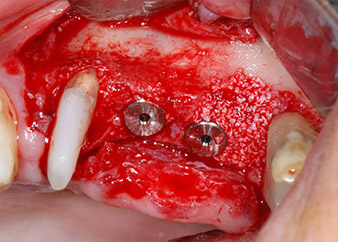

Имплантите (Restore, Keystone Dental, диаметър 3,75 mm, дължина 8.0 mm) са поставени с имплантологичен мотор

(Фиг. 11 и 12).

готовност за покривни винтове

Фиг. 12: Двата импланта са на място и са готови за поставяне на покривни винтове.